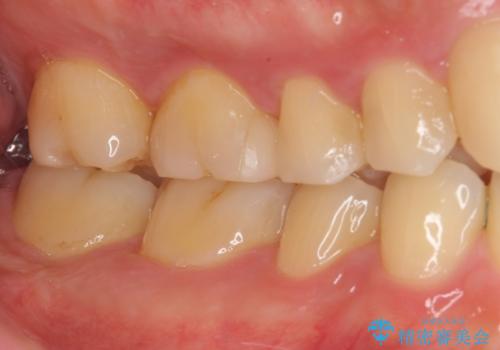

銀歯とその下の虫歯を除去し、形を整え、精度の良いシリコーンによる型どりを行いました。

セラミックインレーを接着する際は、ラバーダム防湿を行いました。

精度の高い詰め物は、二次う蝕になりにくいです。